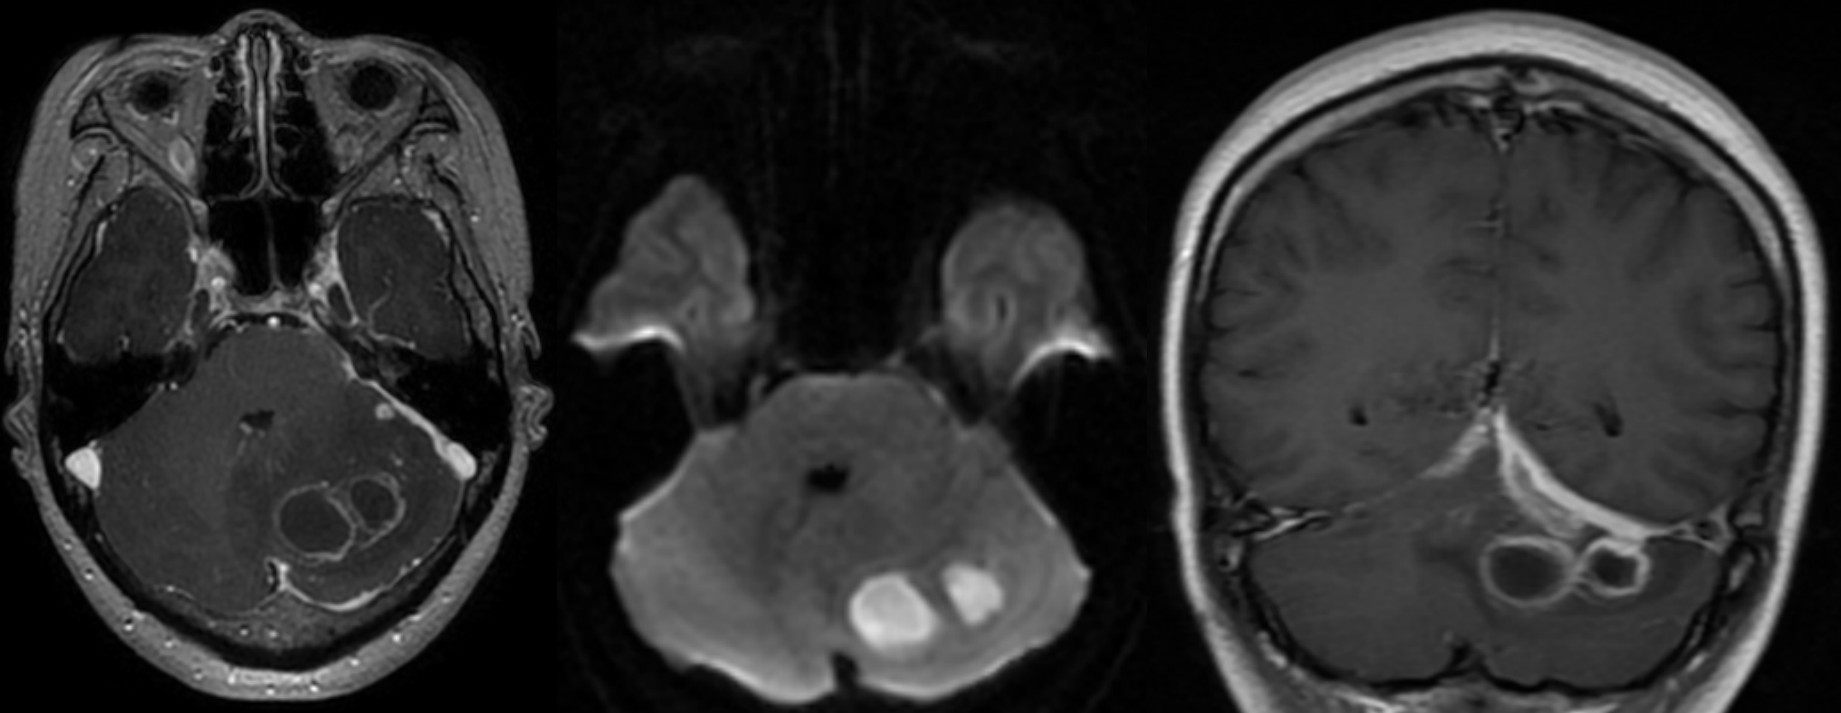

头颅MRI提示双侧小脑幕下、左侧小脑半球脑膜炎并脓肿形成?

复查头颅MRI提示小脑幕下脓肿较前缩小。